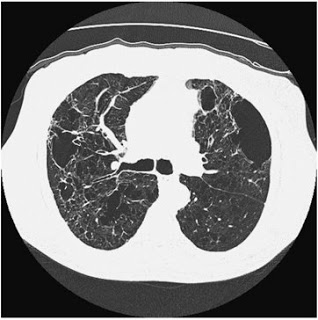

Beyond plain sections of tissue on a slide, there are many ways to observe pathology: fluorescent staining (FISH), staining for various microbial organisms, electron microscopy to delineate finer details, as well as other methods such as radiologic exams (CT scans, PET scans, etc.) These images can be striking for two very different reasons: they can diagnose a very serious disease such as cancer, and they can be aesthetically beautiful.

In Hidden Beauty: Exploring the Aesthetics of Medical Science, a large collection of beautiful albeit pathological images are compiled to serve as both art and education. As one of the authors, pathologist Dr. Iacabuzio-Donahue, points out, most people better understand concepts when they are presented visually. A complex disease can be explained by pictures and diagrams. I find that drawing even rough representations for patients allows them to have a clearer understanding of what is going on. Showing them a CT scan of their lungs damaged by COPD is far more poignant than explaining in words what smoking does to the lungs. Likewise, showing people how the normal becomes abnormal as seen under a microscope can be very useful.